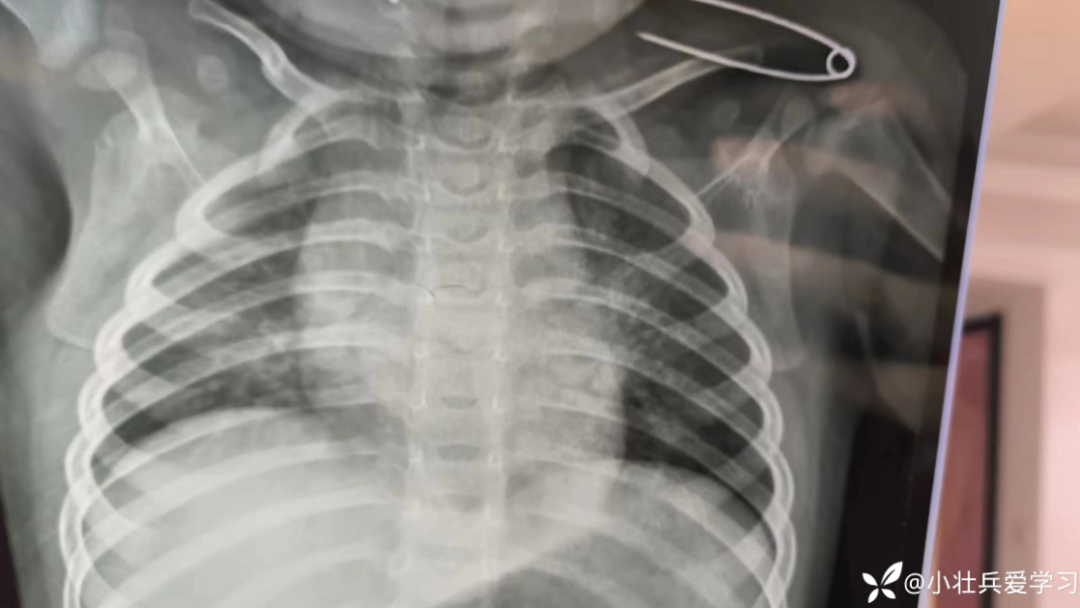

复查胸片